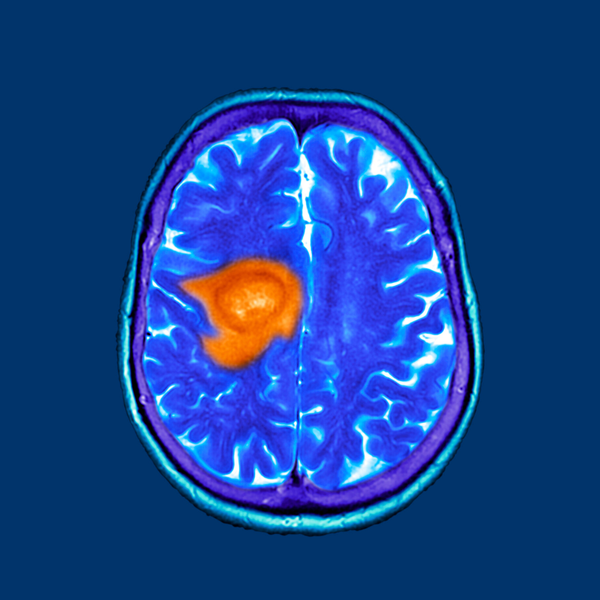

O glioblastoma, também conhecido como glioblastoma multiforme, é um tipo de câncer cerebral altamente agressivo e incurável. Neste artigo, exploraremos diversos aspectos dessa doença devastadora, incluindo sua nomenclatura, epidemiologia, diagnóstico, tratamento, cirurgia máxima segura e opções complementares de tratamento, levando em consideração a situação clínica do paciente. Nomenclatura e Epidemiologia